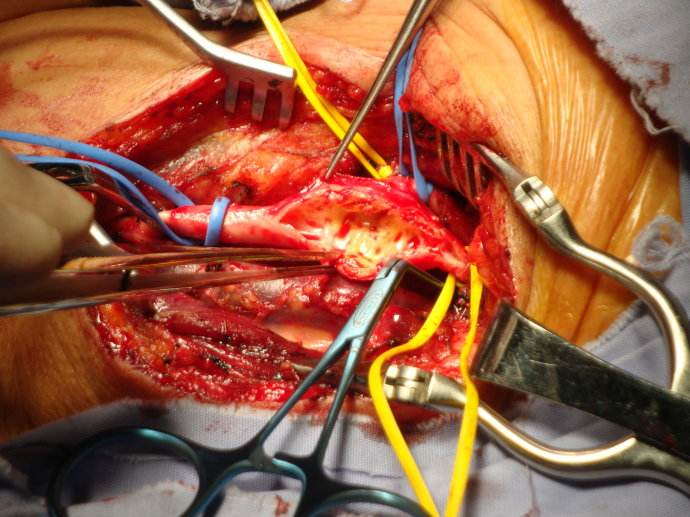

治療腦梗塞手術

小腦腦梗塞手術

手術治療腦梗塞的

手術治療腦梗塞

手術治療中的腦梗塞